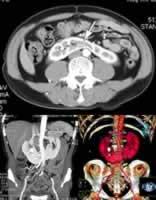

CT扫描可清晰地描绘出肾脏的轮廓,但并非必不可少。对于盆腔融合肾或位于胁腹部者,插入输尿管导管的平片将为诊断提供第一条线索。逆行造影将显示肾盂的位置及因有感染或梗阻所致改变。肾闪烁摄影术可显示出肾块及其轮廓,如同超声影象一般。

在马蹄肾中,峡部常将每侧肾下极连接,每一肾块都低于正常位置。这些肾块的长轴是垂直的,而正常肾轴因沿腰大肌缘排列,相对脊柱呈倾斜的“八”字。极少数情形下,两肾块融合为一,其内含两个肾盂及两根输尿管。这样的肾块可位于中线,输尿管开口于固定位置(合并融合的交叉异位肾)。

①马蹄肾者肾盂位于肾块的前表面,而正常肾脏的肾盂则位于肾脏的内侧。对马蹄肾而言,最有诊断价值的线索是肾下极肾盏表现为朝向中线,且比输尿管更靠近中线。

②交叉异位的融合肾显示出2个肾盂及2根输尿管,其中一根必须越过中线才能在膀胱固有位置排尿。

③一饼状或块状的肾脏中位于骨盆(盆腔融合肾),但其输尿管及肾盂可显影,并可压迫膀胱顶部。